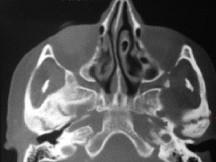

问题 关于颞下颌关节强直(如图)的描述哪项是正确的 ( )

选项 A.颞下颌关节外强直是关节外纤维黏连 B.颞下颌关节内强直是关节内骨性黏连 C.混合性下关节强直是指关节内,外强直同时发生,又称颌间挛缩 D.关节及关节周围组织器质性病变造成开口困难或完全不能开口 E.颞下颌关节强直常常突然发生

答案 D